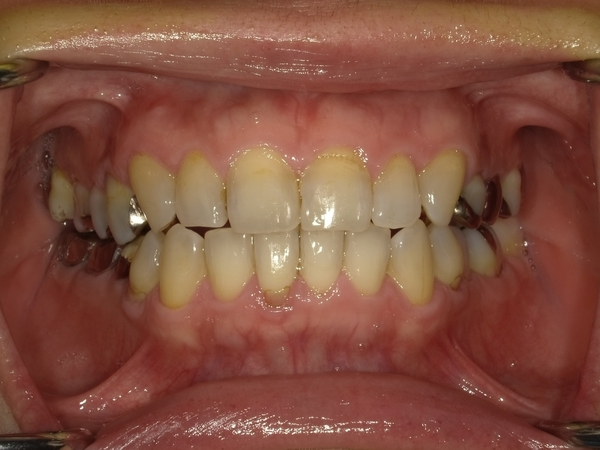

ガタガタとした歯並びや八重歯(叢生)CASE8